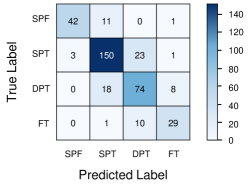

We trained a convolutional neural network (CNN) to classify four severities of burns: SPF (superficial), SPT (superficial partial thickness), DPT (deep partial thickness), and FT (full thickness). We built a saliency mapping method, Boundary Attention Mapping (BAM), that utilises this trained CNN for the purpose of accurately localizing and segmenting the burn regions from skin burn images. We demonstrated the effectiveness of our proposed pipeline through extensive experiments and evaluations using two datasets; 1) A larger skin burn image dataset consisting of 1684 skin burn images of four burn severities, 2) An LDI dataset that consists of a total of 184 skin burn images with their associated LDI scans. The CNN trained using the first dataset achieved an average F1-Score of 78% and micro/macro- average ROC of 85% in classifying the four burn severities. Moreover, a comparison between the BAM results and LDI results for measuring injury boundary showed that the segmentations generated by our method achieved 91.60% accuracy, 78.17% sensitivity, and 93.37% specificity.

The Boundary Attention Mapper (BAM) methodology of creating saliency maps, dependent on information in various layers of a convolutional neural network (CNN), allows us to generate fine-grained segmentations of the burn injury from images. We trained a CNN, with a pre-trained EfficientNetB7 architecture, on 1684 burn images, to classify four severities of burns: SPF (superficial), SPT (superficial partial thickness), DPT (deep partial thickness), and FT (full thickness). The CNN achieved an average F1-Score of 78% (Table 1) and micro/macro- average ROC of 85% (Figure 1a). A confusion matrix illustrates true and predicted values, therefore illustrating the true positive and negative error rates of the system. The matrix identifies that misclassification between burn severity classes is highest between adjacent classes of severity, for example SPT and DPT (Figure 1b).